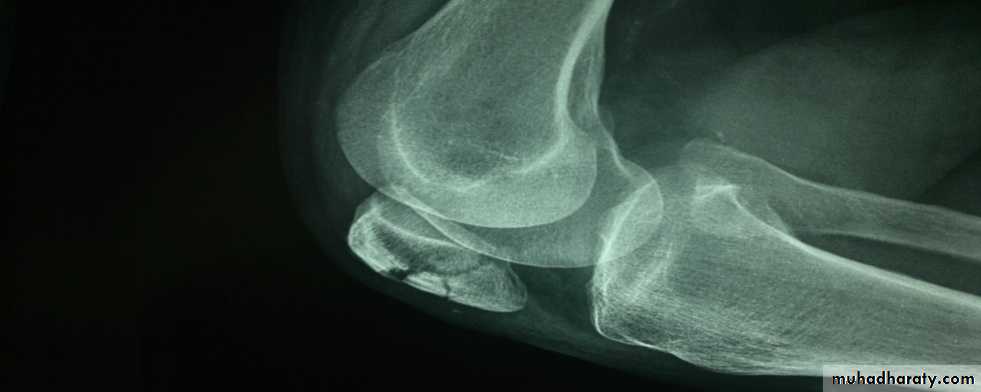

Supracondylar fracture femur

In children and adolescents- usually Salter-Harris II injury.Distal fragment tilted backward by gastrocnemius muscle.

Check distal pulses.

Supracondylar fracture-child